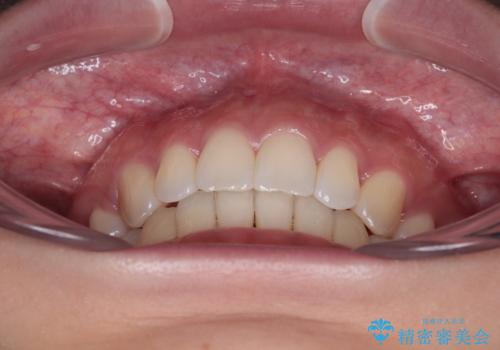

舌の突出癖を改善するためのトレーニングをしっかりと行っていただいたことで、比較的スムーズに治療を進めることができました。

口元の突出感もしっかりと改善することができました。